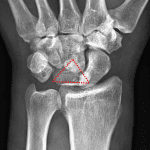

- Acute lunate dislocation with 90 degrees volar tilt and 1 cm volar displacement of the lunate

- Tiny ossific densities project along the dorsal aspect of the proximal carpal row

- Lunate dislocation

Acute lunate dislocation with 90 degrees volar tilt and 1 cm volar displacement of the lunate.

Tiny ossific densities project along the dorsal aspect of the proximal carpal row, which may represent tiny chip/avulsion fractures. No additional fracture identified.